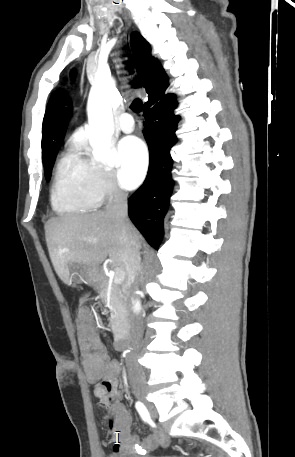

В компьютерном томографе излучатель рентгеновских лучей установлен в кольцевой части аппарата и, непрерывно вращаясь вокруг зоны исследования, производит послойное сканирование в различных плоскостях. В результате получаются снимки анатомической зоны в мельчайших подробностях, а после цифровой обработки полученных данных – точные трехмерные объемные модели исследуемой области. При этом изображения органов можно приблизить, повернуть в разные стороны, что значительно повышает точность диагностики различных заболеваний.

Для улучшения визуализации мягкотканных структур (внутренних органов, клетчаточных пространств, связок, мышц, сухожилий, кровеносных сосудов и лимфатических узлов) в ряде случаев проводится дополнительно контрастное усиление. Для этого пациенту внутривенно вводится йодсодержащий контрастный препарат, который активно поглощает рентгеновские лучи. Благодаря способности контраста накапливаться в патологических участках, они становятся хорошо видны на снимках КТ. Контрастное усиление позволяет оценить состояние сосудистой системы, выявить участки воспаления и опухолевые образования. С помощью контрастирования удается выявлять опухоли минимальных размеров, определить точные размеры и границы опухоли, степень ее воздействия на окружающие ткани.